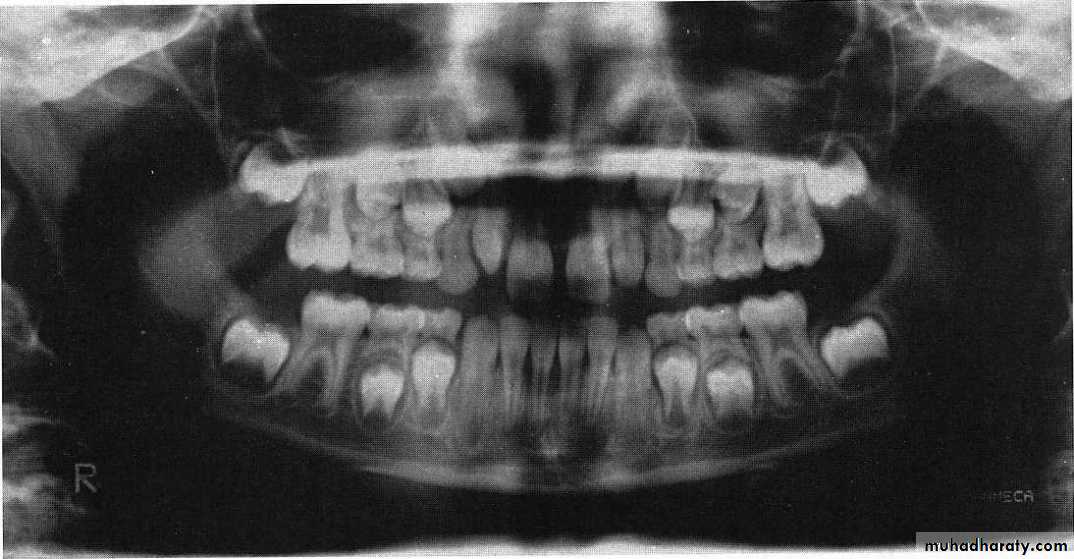

Panoramic is recommended at approximately the time of the early mixed dentition to assess

1. the dental age of the patient and

2. to aid in the early diagnosis of congenital and developmental anomalies.Panoramic radiograph

A diagnostic film includes

the teeth,the supporting structure,

the maxillary region extending to the superior third of the orbit,

the entire mandible including the temporomandibular joint region.

Panoramic used to diagnose:

Condylar fractures,traumatic cysts,

and anomalies that might have gone undetected with the routine periapical survey.

Patient’ age nearly 9 because the lower canines erupted and their eruption on 9-10 year and the upper lateral emerging now

This child is 7-8 years old because he has the upper maxillar centrals erupted (depending on schedule of time of eruption of permanent teeth (eruption lecture)